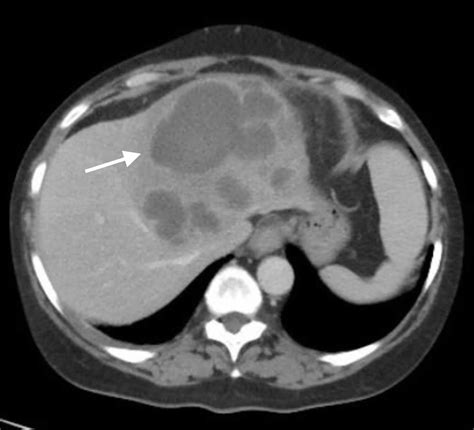

Diagnosing a liver abscess involves a combination of medical history, physical examination, and diagnostic tests. Imaging studies such as ultrasound, CT scans, and MRI are commonly used to visualize the abscess. Blood tests can help identify the underlying infection, and sometimes, a sample of the abscess fluid may be taken for culture and sensitivity testing.

A liver abscess is a collection of pus that forms in the liver, often due to an infection. This condition can be life-threatening if not treated promptly. Liver abscesses can be classified into two main types: pyogenic (bacterial) and amebic (parasitic). Each type has distinct causes and treatment approaches.